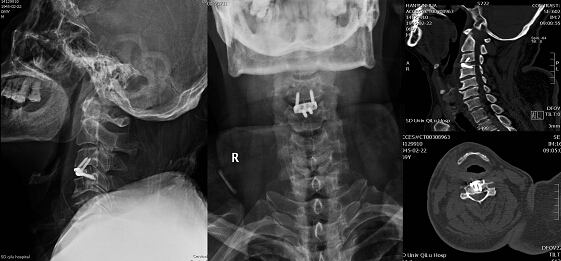

病例2:患者为一53岁男性,因左侧躯体皮肤浅感觉减退2年入院。患者2年前无明显诱因出现左侧躯干部皮肤痛、温感觉减退,呈进行性加重。近日患者感症状明显加重,于当地医院行颈部MRI 检查示:颈5-6、颈6-7椎间盘突出,脊髓空洞症,小脑扁桃体下疝,颈椎退行性变。入院诊断:1.小脑扁桃体下疝畸形;2.脊髓空洞症;3.颈椎间盘突出并椎管狭窄。

患者同时合并小脑扁桃体下疝畸形和颈椎间盘突出导致患者脊髓空洞症,引起症状。神经外科脊髓脊柱专业组经充分讨论后,为患者制定颈后路枕肌下减压术+颈前路颈5-6椎间盘显微切除并椎间融合的联合手术方案。手术于2014年12月23日实施,术中先行后路小骨窗枕肌下减压术。后于显微镜下行颈前路颈5-6椎间盘切除并应用强生公司的Zero-P零切迹椎间融合器行颈椎间融合术。术后患者躯体皮肤感觉异常症状较术前明显改善,并主诉无明显吞咽困难或吞咽不适的症状。术后复查颈椎平片及CT示效果满意(图4 B)。

图4

近年来,我院神经外科脊柱脊髓专业组在江玉泉的带领下,成功开展了大量颈椎病前、后路的显微微创手术治疗。近期神经外科于我院率先开展使用了Zero-P零切迹椎间融合器行颈前路颈间融合手术,患者术后均无明显吞咽困难或吞咽异物感,大大降低了患者术后的不适感。与传统的颈前路椎间融合器置入加椎体前钛板固定椎间融合技术相比,Zero-P零切迹椎间融合术后患者吞咽困难、吞咽异物感及术后不适感的发生率显著降低(图4)。